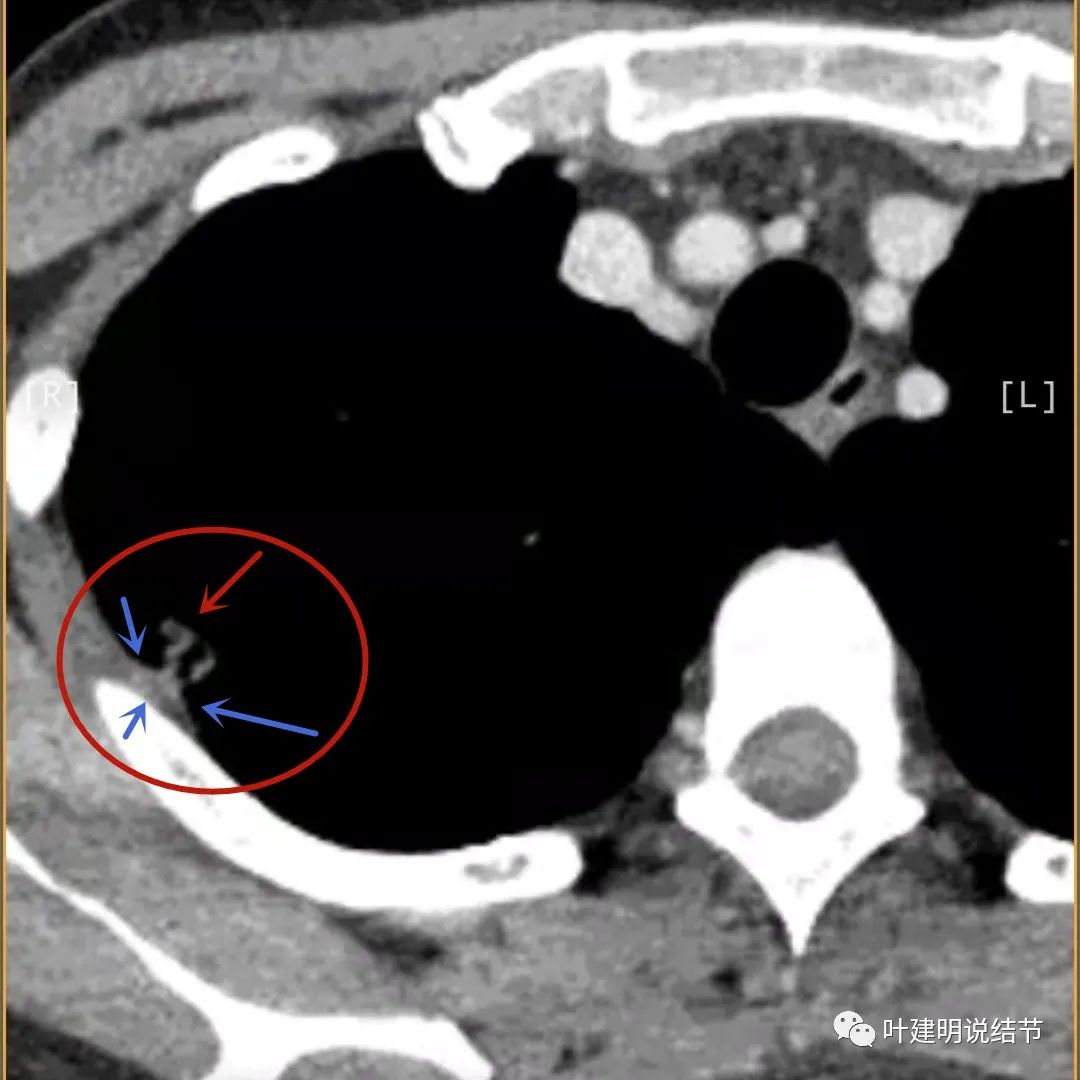

蓝色箭头所指处居然有低密度影,难道是坏死?因为比肌肉密度低,也无强化,况且主病灶的中间也有个低密度的小点状

病灶有明显强化(说明炎性可能性大,如果恶性这样强化,血供丰富,应该倍增速度更快。蓝色箭头示胸膜处低于软组织密度的区域;桔色箭头示病灶边缘平直缺乏膨胀性;黄色箭头示中间的空腔

邻近胸膜处的增厚密度低于肌肉组织,病灶强化明显且均匀